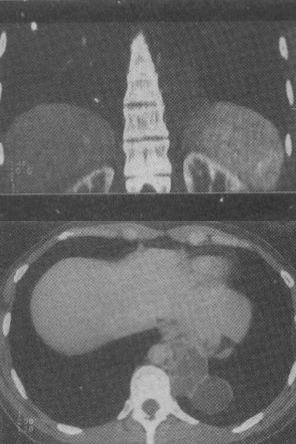

患者男,18岁,无明显症状,体检行CT检查如图,最可能的诊断为

A.左下肺膈疝

B.左下肺肺隔离症

C.左下肺癌

D.神经纤维瘤

E.左下肺肺炎

男,18岁,无明显症状,体检行CT检查如图,最可能的诊断为()<img border="0" style="width: 365px; height: 274px;

[单选题]男,18岁,无明显症状,体检行CT检查如图,最可能的诊断为()A.左下肺膈疝B.左下肺肺隔离症C.左下肺癌D.神经纤维瘤E.左下肺肺炎

男,18岁,无明显症状,CT检查如图。最可能的诊断为()<img border="0" style="width: 345px; height: 194px;&qu

[单选题]男,18岁,无明显症状,CT检查如图。最可能的诊断为()A.左下肺膈疝B.左下肺肺隔离症C.左下肺癌D.神经纤维瘤E.左下肺肺炎

患者男,18岁,无明显症状,体检行CT检查如图,最可能的诊断为( )。<br /><img border="0" style="width: 442p

[单选题]患者男,18岁,无明显症状,体检行CT检查如图,最可能的诊断为( )。A.左下肺膈疝B.左下肺肺隔离症C.左下肺癌D.神经纤维瘤E.左下肺肺炎